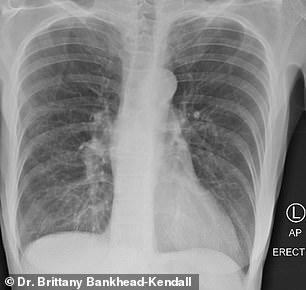

Koronavirüsü ile enfekte bir akciğerin şok edici resimleriFotoğraflar, geçen yıl salgın patlak verdiğinden bu yana binlerce korona hastasını tedavi eden Texas Tech Üniversitesi Sağlık Bilimleri Merkezi'nde yardımcı doçent olan Dr. Brittany Bankhead-Kendall tarafından paylaşıldı.

Görüntüler, normal bir kişinin akciğerlerini, sigara içen kişinin akciğerlerini ve koronavirüs bulaşmış bir hastanın akciğerlerini gösteriyor.

Normal akciğerler koyu ve şeffaf bir şekilde görünürken; sigara içen kişinin akciğeri ise kısmen beyaz görünüyor ve bazı yara izleri bulunuyor.

Koronavirüs ile enfekte olan bir kişinin akciğeri ise, bazı kısımlarda neredeyse tamamen opak görülüyor.

Akciğeri görüntülerini değerlendiren Dr. Brittany Twitter'da şunları yazdı: "Bunu kimin duyması gerektiğini bilmiyorum, ancak bir kovid enfeksiyonundan sonra akciğerler, şimdiye kadar gördüğümüz en yoğun sigara içenlerin akciğerlerinden daha kötü görünüyor. Çöküyorlar, kan pıhtılaşıyor ve nefes darlığı devam ediyor ...".

Koronavirüsü ile enfekte olmuş bir akciğerin filmi... Semptomsuzlarda bile vakalar çoktur

Dr. Brittany, ayrıca tedavi ettiği kişiler arasında, semptomları olanlarda göğüs röntgenlerinin beklemediği kadar kötü olduğunu açıkladı. “Ve semptom göstermeyen insanlarda bile, X ışınları vakaların yaklaşık dörtte üçü kadar kötüydü”, diye ekledi.